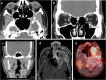

Meckel's cave is a dural recess in the posteromedial portion of the middle cranial fossa that acts as a conduit for the trigeminal nerve between the prepontine cistern and the cavernous sinus, and houses the Gasserian ganglion and proximal rootlets of the trigeminal nerve. It serves as a major pathway in perineural spread of pathologies such as head and neck neoplasms, automatically upstaging tumours, and is a key structure to assess in cases of trigeminal neuralgia. The purpose of this pictorial review is threefold: (1) to review the normal anatomy of Meckel's cave; (2) to describe imaging findings that identify disease involving Meckel's cave; (3) to present case examples of trigeminal and non-trigeminal processes affecting Meckel's cave.

Teaching points: • Meckel's cave contains the trigeminal nerve between prepontine cistern and cavernous sinus. • Assessment is essential for perineural spread of disease and trigeminal neuralgia. • Key imaging: neural enhancement, enlargement, perineural fat/CSF effacement, skull base foraminal changes.